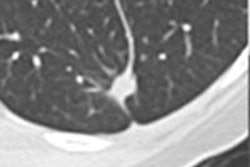

Example of an "indicate question" in VQuest. The student is asked to mark an anatomical structure in the volumetric image. Students can scroll through the image, change contrast settings manually or with the preset window/level menu, or change viewing direction by clicking the buttons (A, S, and C). The teacher decides which manipulation tools the students are allowed to use during the test or for a particular question. All images courtesy of Dr. Cécile Ravesloot.

Example of a question in which students are asked to name the marked structure. In this case, they need to choose from a long list of options, which they can only open by typing at least two letters of their answer. All alternatives including these two letters are then shown, and the student can click on the preferred answer. This allows for automatic answer checking.